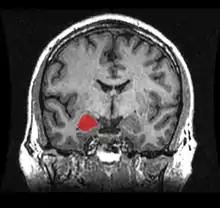

Frontal and side view of amygdala

Amygdala along with other subcortical regions, in glass brain.